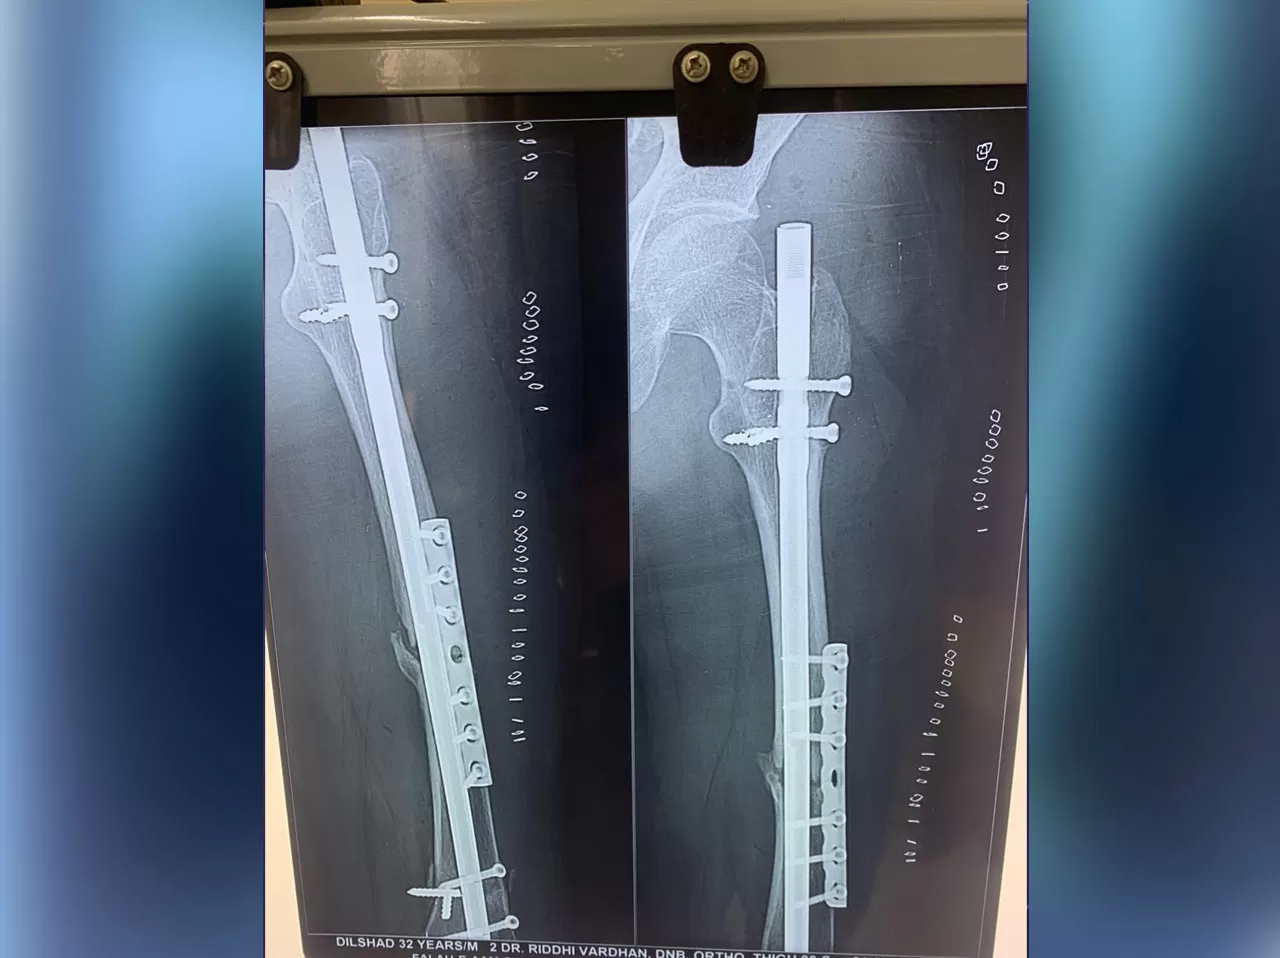

Mr. Dilshad

Name: Mr. Dilshad

Date of Operation: 10 May 2021

Age: 32 Years

Complex Trauma